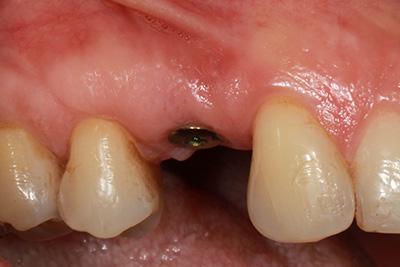

Implants in position and waiting on integration – 4 to 6 Month